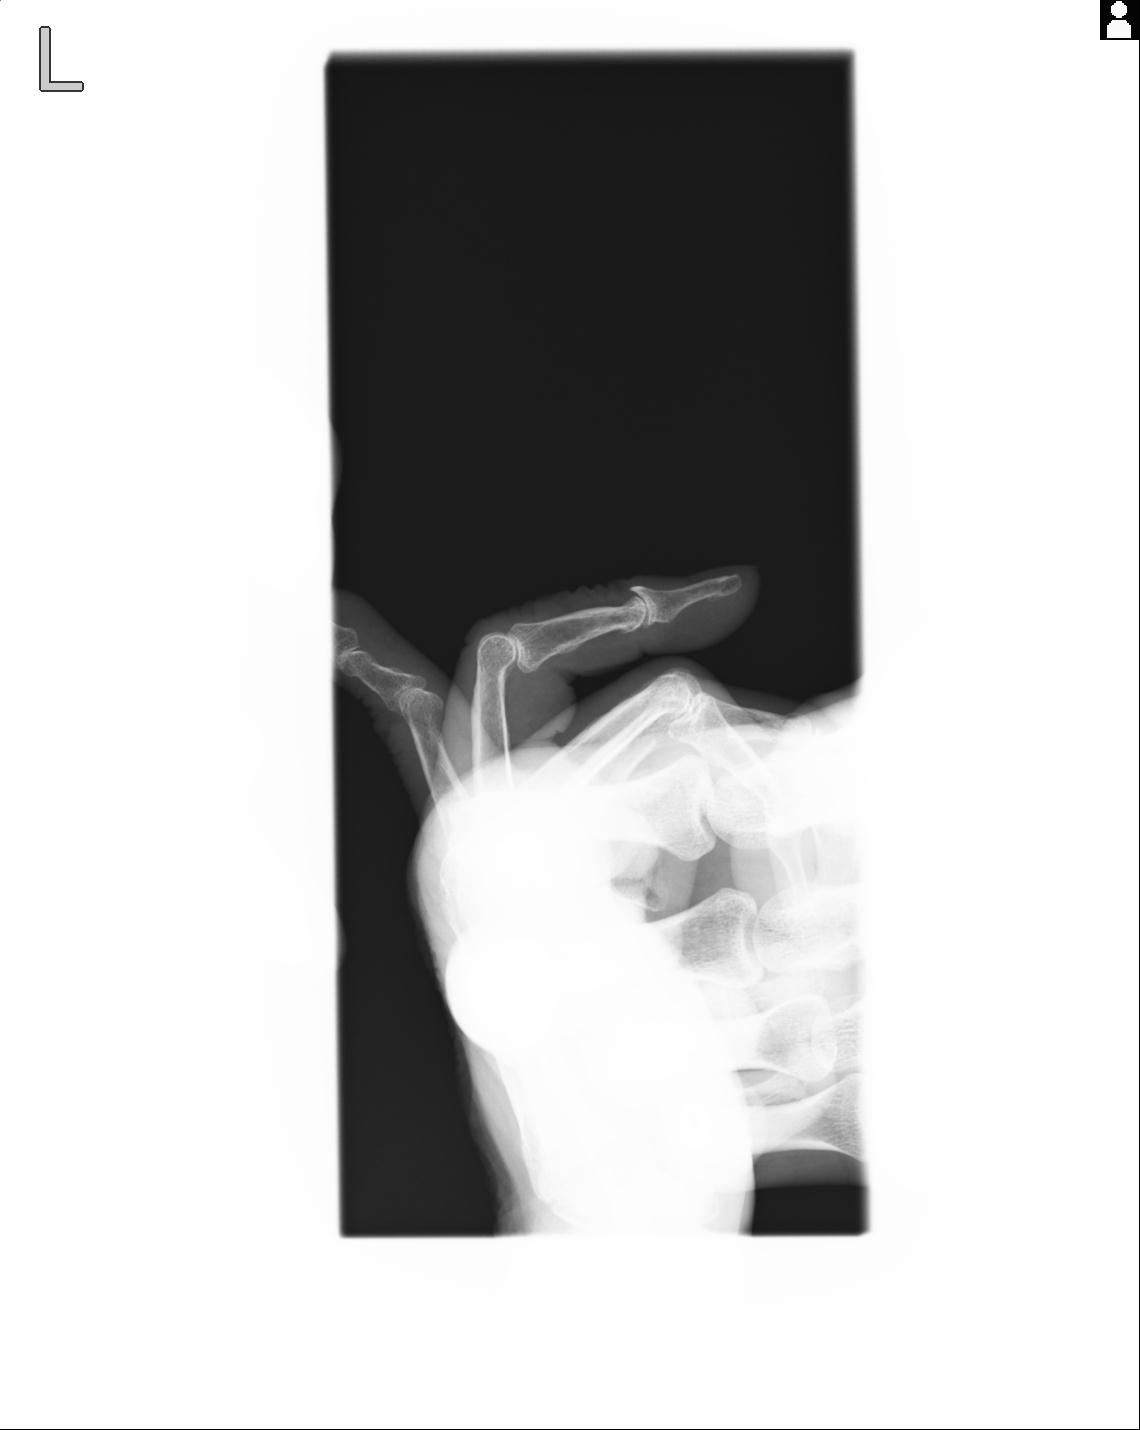

102766 1/5 1/12 左手関節 4R 28歳男性 左橈骨遠位端